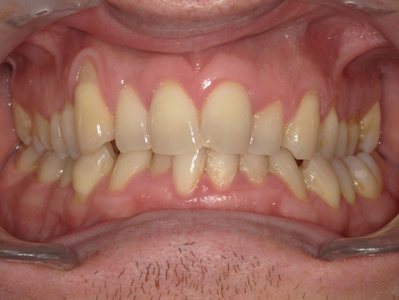

Présentation cas n°1 :